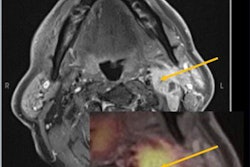

A 24-year-old man with a suspected GIII anaplastic astrocytoma IDH-mutant recurrence, referred for a PET/MRI. 3D Fat-saturated T1 with gadolinium sequence (A) shows enhanced lesions along the left temporal horn. Fused PET/MRI (B) highlights the high F-18 fluorodopa (FDOPA) uptake by the lesions (TBRmean = 2.3; TBRmax = 4.7; TSRmean = 1.2; TSRmax = 2.5; metabolic tumor volume = 29.71 cm3). The dynamic curve shows a washout pattern (slope = −5.42 h-1) (c, slope dark blue dotted line). Axial CBV reveals more voluminous areas (white arrow) that correspond to increased tumor angiogenesis (yellow line: lesion, blue line: contralateral normal brain parenchyma) (D, E). Follow-up MRI one month after the PET/MRI, confirms progression according to the Response Assessment in Neuro-Oncology (RANO) criteria. Figure courtesy of Dr. Laura Rozenblum et al, and European Radiology.Surgery or the clinical-radiological six-month follow-up identified 71 progressions and 35 treatment-related changes. TBRmean, with a threshold of 1.8, best-differentiated glioma recurrence/progression from post-treatment changes in the whole population (sensitivity 82%, specificity 71%, p < 0.0001) whereas curve slope was only significantly different in IDH-mutant high-grade gliomas (HGGs, n = 25), the authors found.